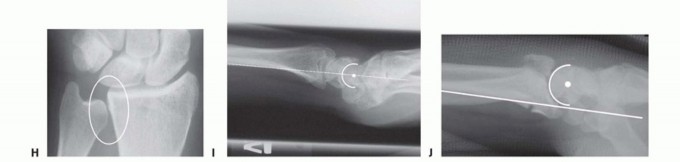

FIG 3 • Pathogenesis of dorsal radius fractures. A. Dorsal bending. B. Volar bending. C. Dorsal shear. D. Volar shear. E. Radial shear. F. Three-part articular. G. Comminuted articular. H. Carpal avulsion. I. High energy.

FIG 4 • A. Positioning for standard lateral radiography. B. Standard lateral radiograph. C. Positioning for 10-degree lateral radiography. D. Ten-degree lateral radiograph. Note the improved visualization of the articular surface of the base of the scaphoid facet and the entire lunate facet. Injuries from a high-energy mechanism present as complex comminuted fractures of the articular surface with extension into the radial/ulnar shaft ( FIG 3I).